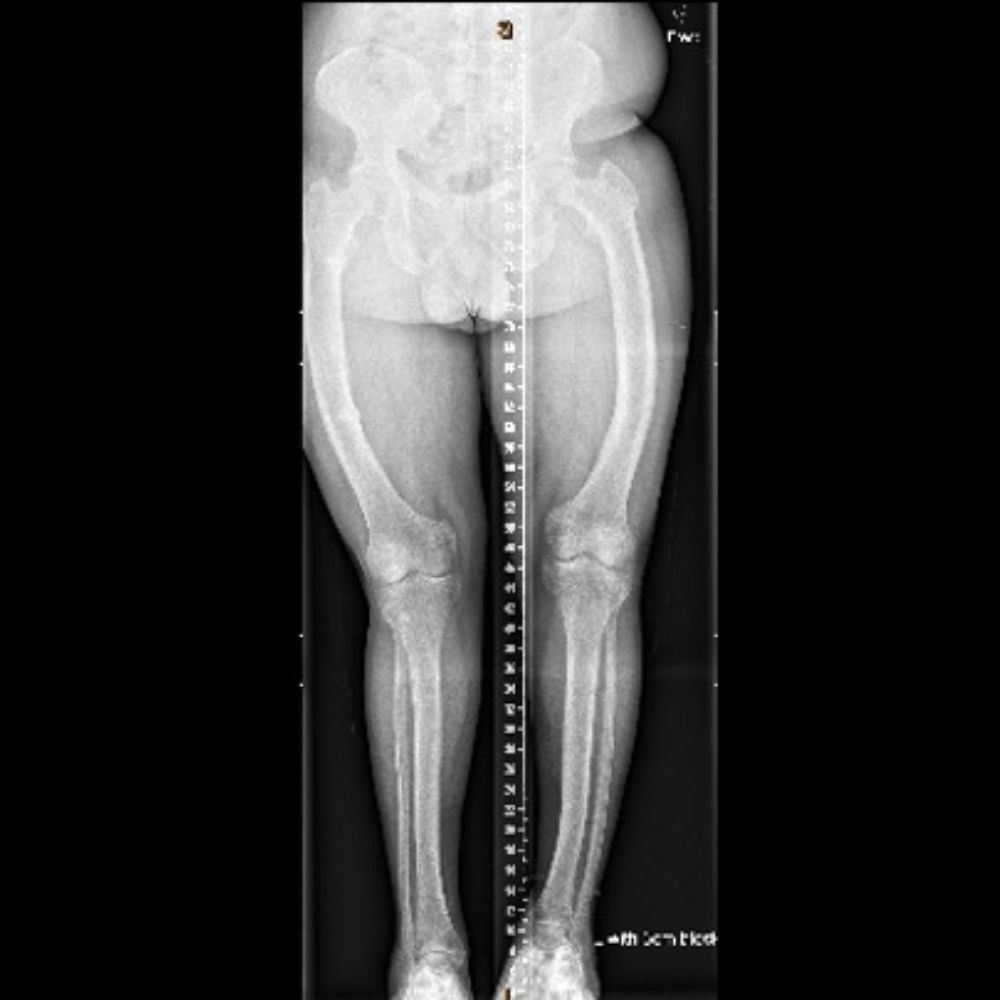

Asymmetric Knock Knee Due to Kidney Problems Through Childhood in 13 Year Old Girl

Knock Knee in Hereditary Spastic Paraparesis in 12 Year Old Girl

Unknown Cause of Bowed Leg in 5 Year Old Boy

Blount's Disease in 17 Year Old Girl